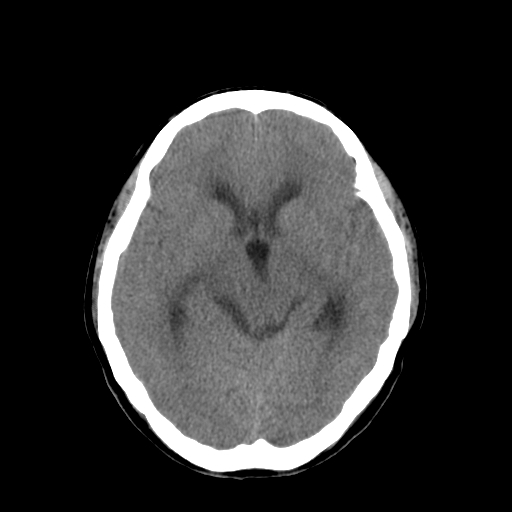

男,34岁,头痛数天。请大家看看是否有占位.

右侧小脑半球占位压迫四脑室并幕上脑积水征像;建议增强或mr检查

梗阻性脑积水,间质性脑肿胀,幕下占位可能,必须进一步检查。

右侧小脑半球占位压迫四脑室并幕上脑积水征像。增强/mri检查。

幕下占位性病变。考虑小脑胶质瘤可能性大